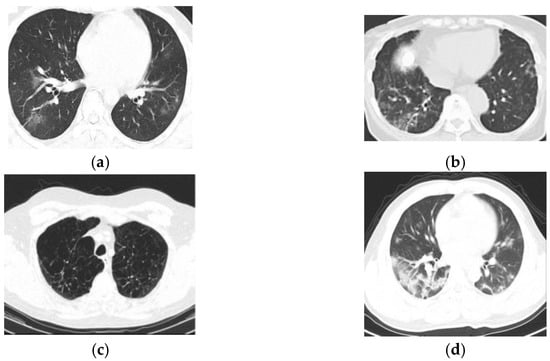

4.2. Description of Dataset

4.3. Experimentation Results

3.1. Acquisition of Input Image